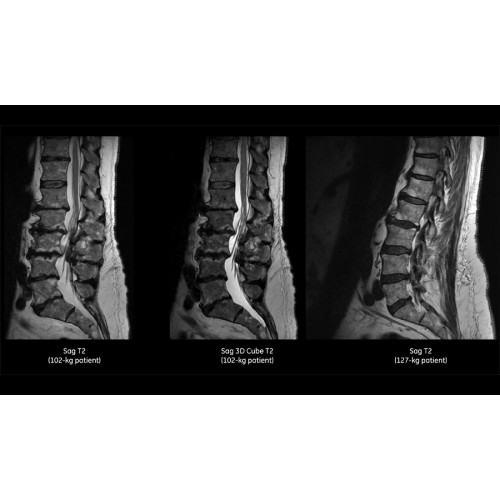

Детализация изображений

Система SIGNA Pioneer воплощает поразительные достижения в области визуализации. Передовая технология Total Digital Imaging (TDI) позволяет добиться большей четкости изображений и на четверть повысить соотношение сигнал/шум.

• Технология Digital Surround Technology (DST) — это новая технология объемной оцифровки данных, объединяющая сигналы от каждого элемента катушки. Прекрасное соотношение сигнал/шум и чувствительность поверхностных катушек в сочетании с превосходной однородностью и высокой проникающей способностью встроенной радиочастотной катушки — все это позволяет создавать качественные изображения не только позвоночника, но и всего тела.

Благодаря революционному программному пакету Silent Suite уровень шума снижается до 77 дБ, что всего на 3 дБ выше уровня окружающей среды. Программный пакет Silent Suite теперь включает полный пакет приложений для исследования ЦНС (T1, T2 FLAIR, DWI10, МРА). Кроме того, мы расширили возможности визуализации Silent за пределы ЦНС для исследований скелетно-мышечной системы и позвоночника. Silent Suite – платформа, содержащая в себе все импульсные последовательности для бесшумного сканирования.